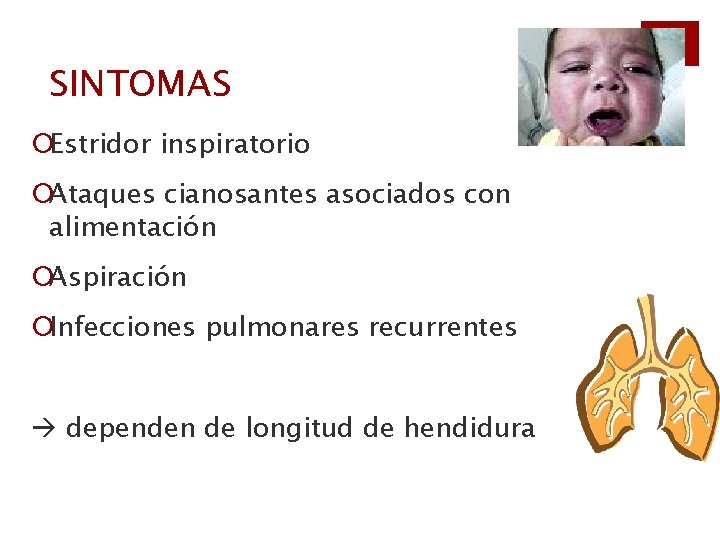

SINTOMAS ¡Estridor inspiratorio ¡Ataques cianosantes asociados con alimentación ¡Aspiración ¡Infecciones pulmonares recurrentes dependen de longitud de hendidura